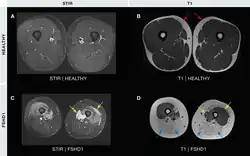

- Magnetic resonance imaging (MRI) is sensitive for detecting muscle damage, even in mild cases. T1-weighted MRI imaging can visualize fatty infiltration of muscles, and T2-weighted MRI imaging can visualize muscle edema. MRI can help differentiate FSHD from other muscle diseases based on the pattern of muscles involved, directing genetic testing.[37][38]